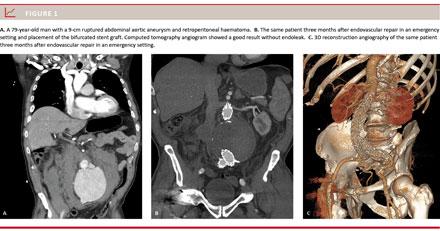

A total of 24 patients (89%) were men and three patients were (11%) women. Patients were aged 65-86 years (mean 74.4 years). The maximal AAA diameter ranged 6-12 cm (mean 8.1 cm). Two cases of ruptured common iliac artery aneurysms were included because of placement of an EVAR stent graft. Six (26%) patients were converted to general anaesthesia due to lack of cooperation or because they became haemodynamically unstable. In five (20%) cases, we chose a percutaneous approach from one side and in one (4%) case a total percutaneous approach. In all other cases (76%), bilateral groin cut-down was performed due to severe calcifications. A bifurcated stent graft was deployed in 26 (96%) of the cases (Figure 1A-C). In one case (4%), an aorto-uniiliac stent graft (Figure 2A-B) was employed followed by femoral crossover bypass.